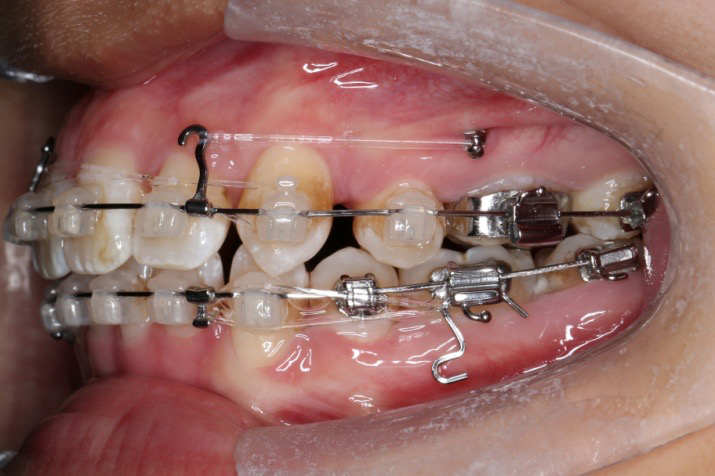

2016.10.31  初戴,0.013cu-niti2017.1.13  上颌加TPA,U56间斜形植入韩国庆北1312-08种植钉,上下0.16cu-niti

2017.02.16  上下0.014*25 cu-niti,50g 拉尖牙远中

2017.04.28

2017.04.28  上0.016*25ss 13、23近远中约5度 v形曲,下0.017*25ss

2017.05.26  磨牙近中倾斜,下颌36、46加power arm

2017.07.25

2017.07.25  上前牙加颈部弹力线